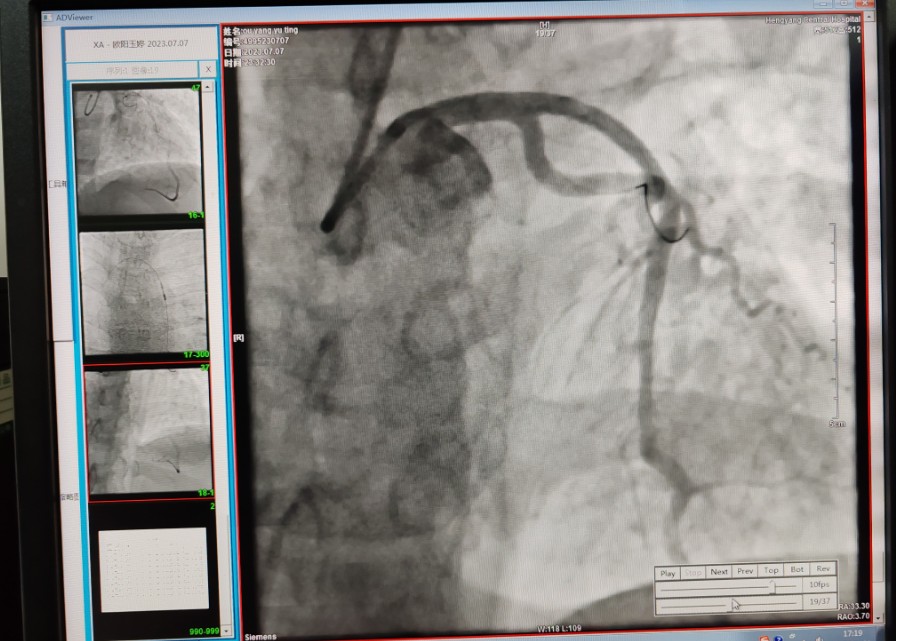

22:29分患者經(jīng)院內(nèi)綠色通道送達(dá)導(dǎo)管室,手術(shù)由雷剛副主任醫(yī)師主刀,楊繼賀副主任醫(yī)師為第一助手,介入技師及護(hù)士密切配合,聞訊而來的趙慶禧主任醫(yī)師坐鎮(zhèn)協(xié)調(diào)指揮。22:37分手術(shù)開始,冠脈造影顯示心臟上最重要的一條冠狀動脈-前降支開口齊頭閉塞,血管粗大且血栓高負(fù)荷,非??简?yàn)介入術(shù)者的手術(shù)能力,一旦發(fā)生冠脈無復(fù)流或操作不慎血栓帶入回旋支導(dǎo)致循環(huán)崩潰,病人幾乎無生還希望;此時,患者手術(shù)臺上仍持續(xù)胸痛,且血氧飽和度在高流量吸氧狀態(tài)下不到80%,雷剛副主任醫(yī)師一方面指揮鎮(zhèn)靜鎮(zhèn)痛及抗心衰治療,一方面緊急啟用IABP(主動脈球囊反搏),然后精細(xì)操控細(xì)如發(fā)絲的介入導(dǎo)絲迅速通過病變,并予冠脈球囊擴(kuò)張、冠脈內(nèi)溶栓、抗痙攣藥物使用、植入冠脈支架,最終成功開通“罪犯”血管,且無手術(shù)并發(fā)癥發(fā)生,整個過程張弛有度、快慢結(jié)合、一氣呵成?;颊咝g(shù)后胸痛明顯好轉(zhuǎn),血氧飽和度上升至96%,術(shù)后1天轉(zhuǎn)出監(jiān)護(hù)病房,第3天拔出IABP,目前已康復(fù)出院。